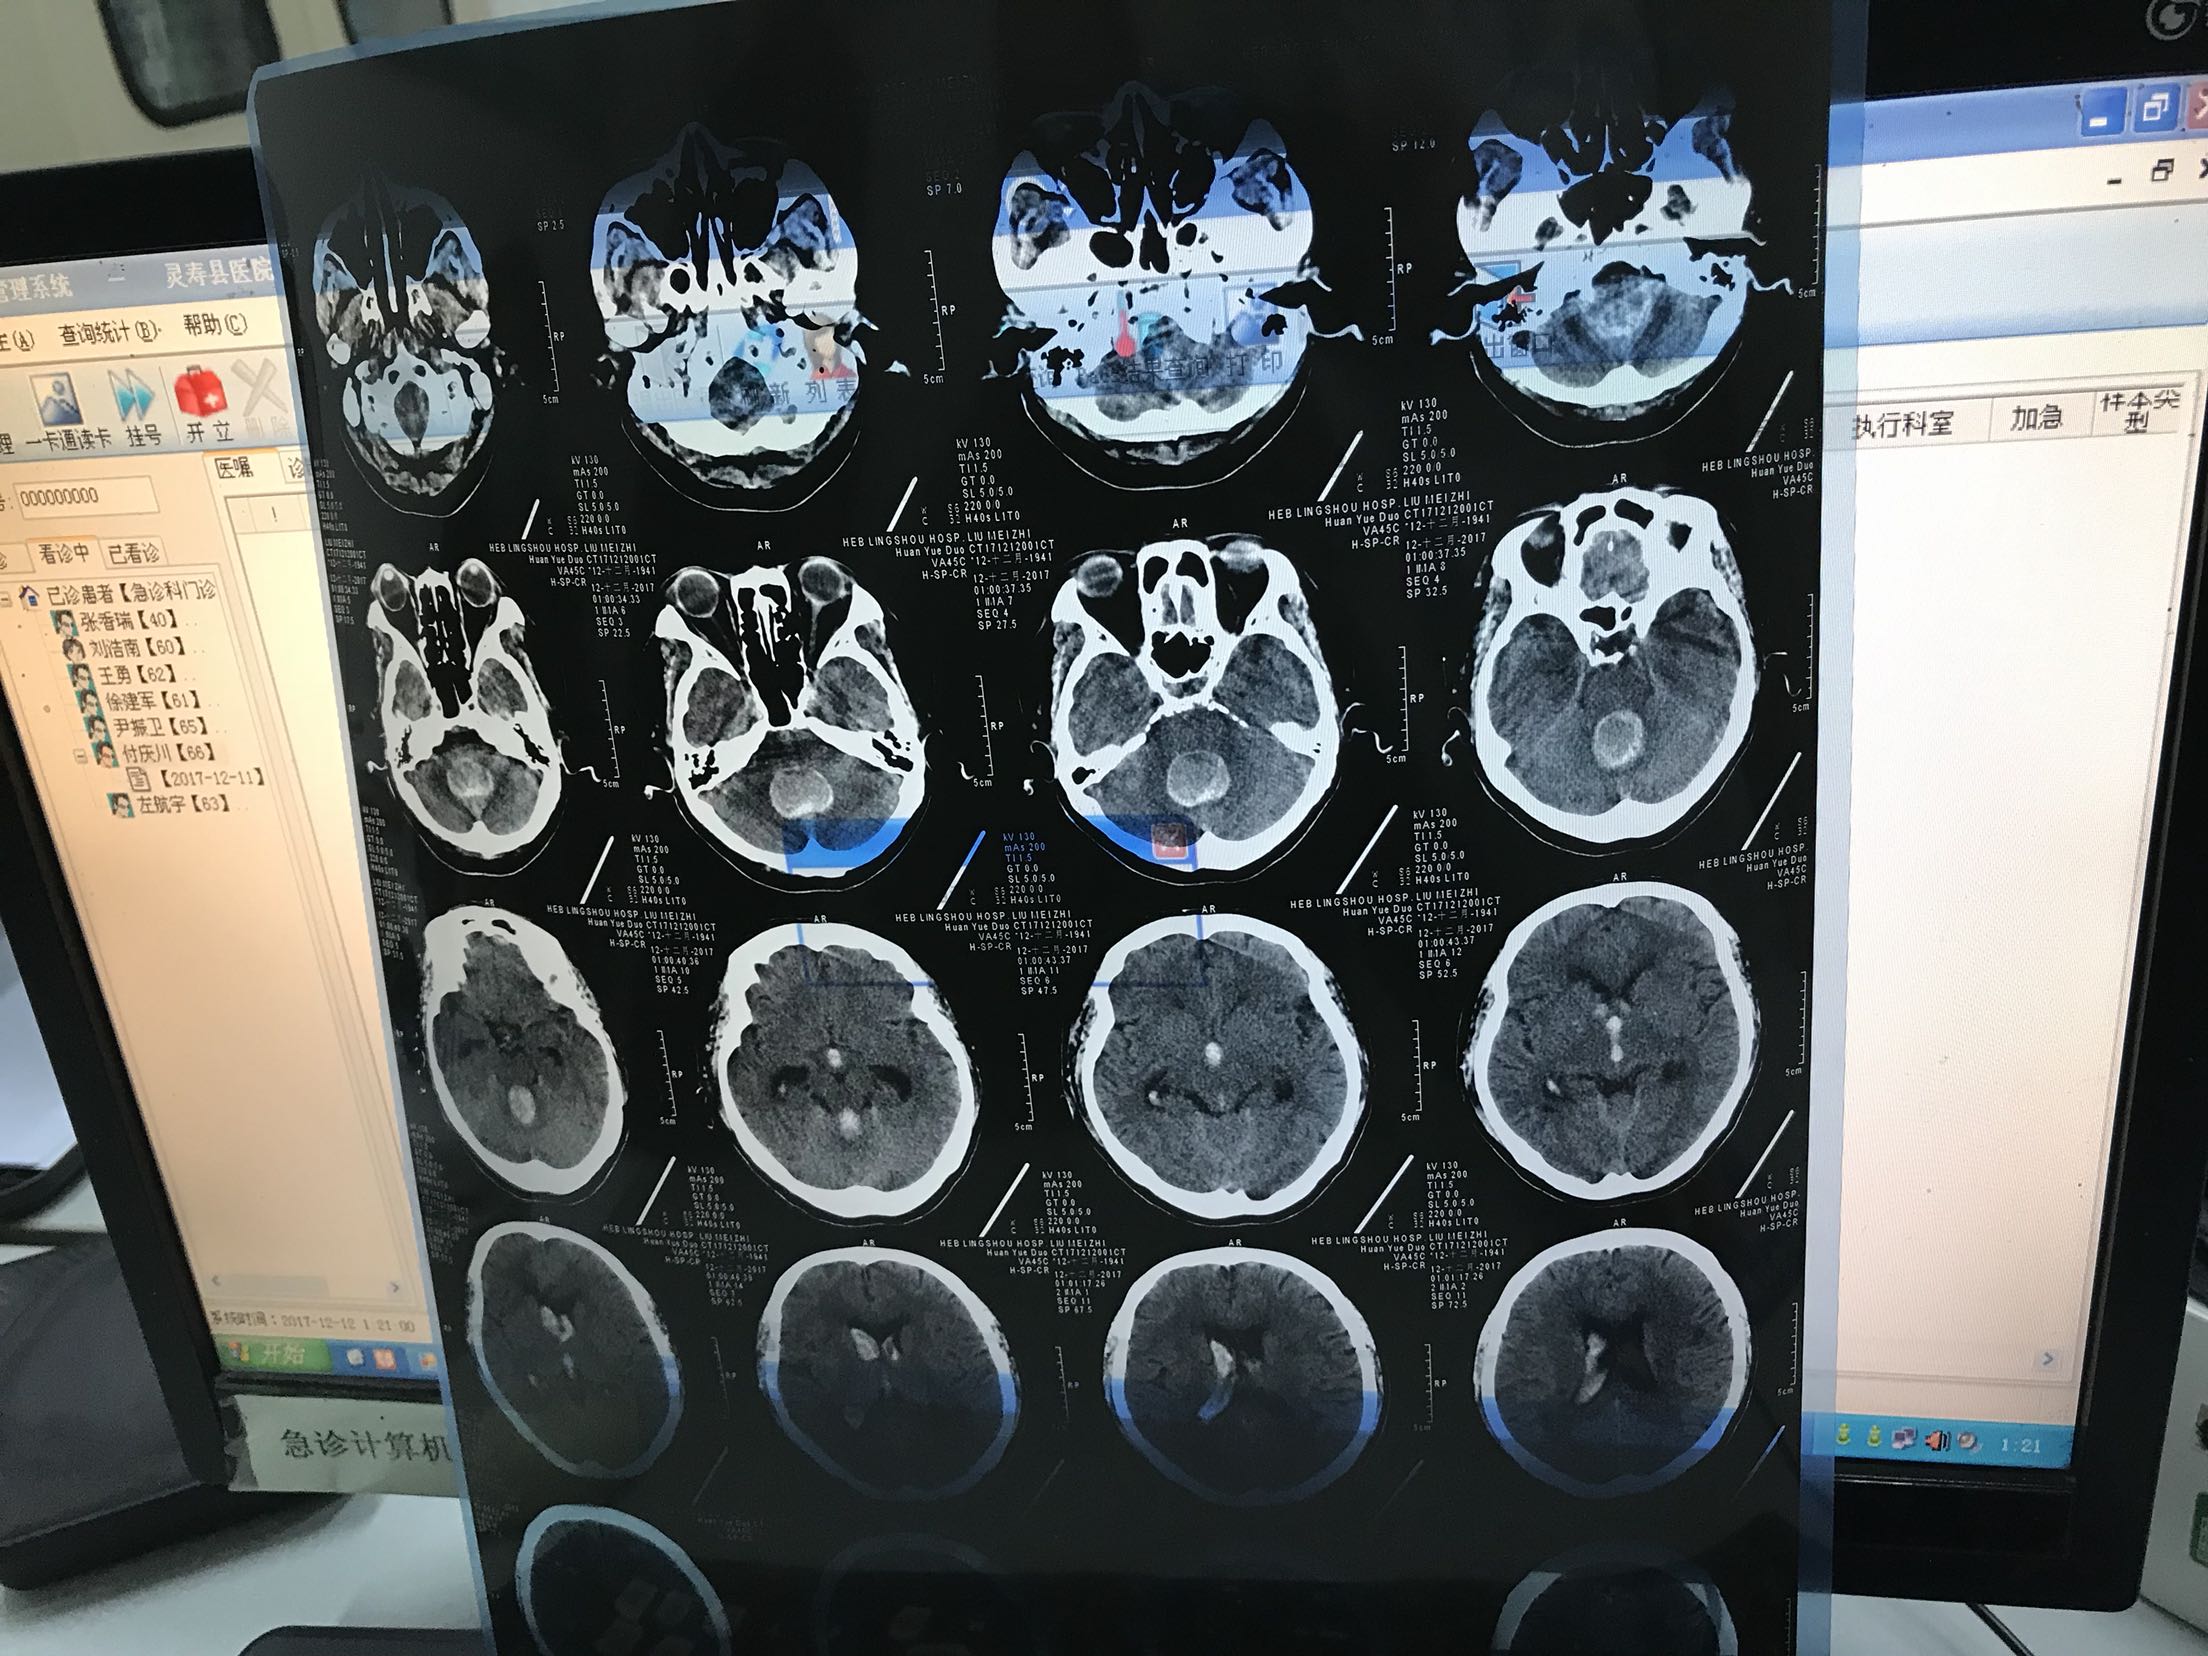

危险的脑出血?

意识不清2小时,打120入院,急诊查CT脑出血

意识不清,压眶反射存在,呼吸急促,四肢肌力不清

脑出血,建议手术